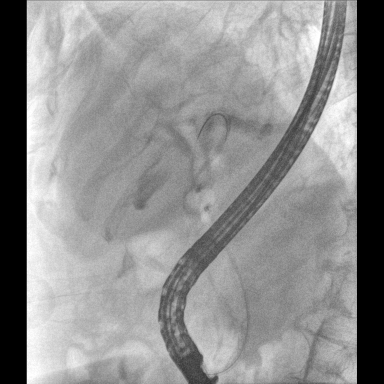

具備血管造影及數(shù)字減影(DSA)、路徑圖(Road-map)、透視、攝影等功能。 廣泛適用于介入科、血管外科、腫瘤科、消化內(nèi)科及骨科等多個(gè)臨床科室,典型應(yīng)用包括:TACE(肝腫瘤栓塞與化療灌注術(shù))、心臟起搏器置入術(shù)、四肢動(dòng)脈造影術(shù)、下肢靜脈濾器置入術(shù)、ERCP(經(jīng)內(nèi)鏡逆行胰膽管造影術(shù))等。

核心DSA軟件可實(shí)時(shí)生成高清血管影像,結(jié)合路徑圖功能,在手術(shù)中為醫(yī)生提供血管導(dǎo)航。